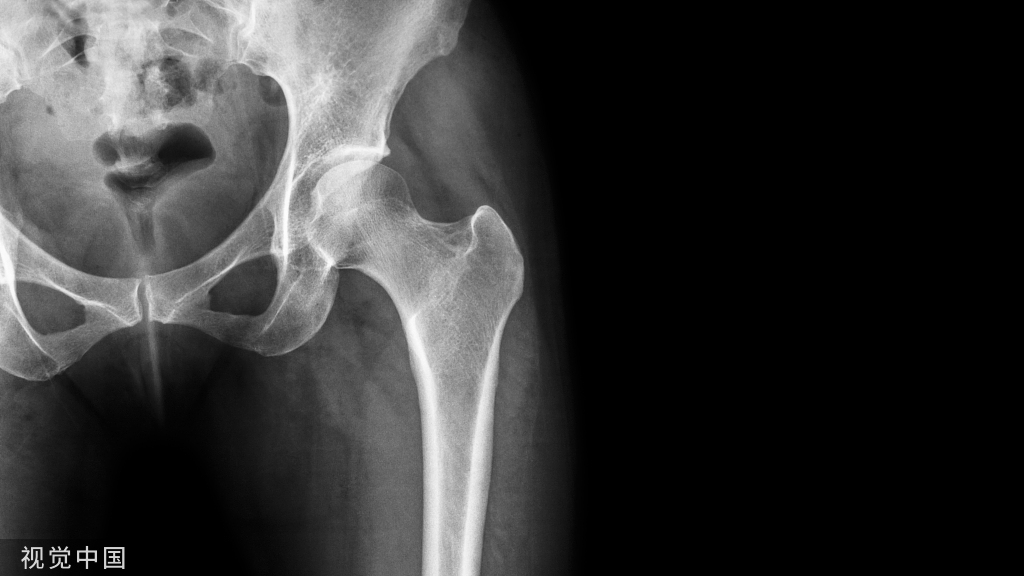

我们管 X 线检查叫 X 光片、照相或拍片。在 X 光片里,我们能看到脊柱有没有骨折,有没有骨质破坏,有没有脊柱侧弯、有没有骨质增生等。一些有经验的大夫,可以通过椎间隙高度的丢失判断椎间盘的退变程度。

但是对于大部分软组织病变如椎间盘、椎管内神经、有没有占位性病变等却无能为力。如果患者有压缩骨折,X 光片也无法判断是新鲜骨折还是陈旧骨折,这样也就无法定制下一步诊疗计划。

所以,X 光片的优点是廉价、检查快捷,缺点是对人体有辐射,组织显像有限,只能看骨头,不能看软组织。

一般来说,X 光片在脊柱外科里,属于一种基础检查或筛查,对绝大多数腰背痛的病人都适用。